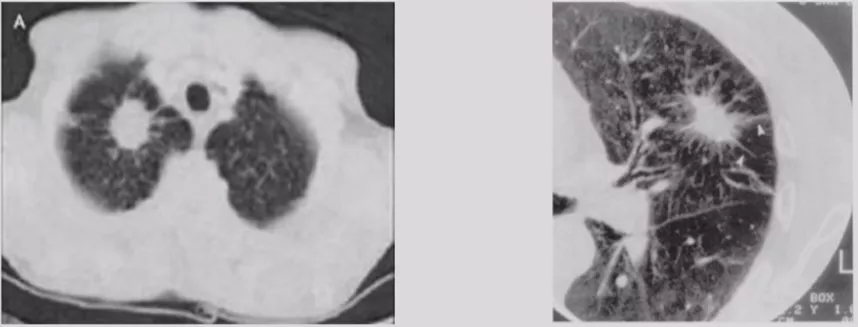

局灶性机化性肺炎

机化性肺炎有一个特点,它会有动态变化,大小和形态都有很大的变异,形态不规则呈多角形,贴近胸膜面(可有局限性胸腔积液)或沿支气管血管束分布,有粗长毛刺、尖角、向心性弓形凹陷、支气管扩张,部分病灶中心可出现低密度区(增强时呈周围强化),部分病灶边缘可见肺泡隔增厚而使边缘清晰,纵膈、肺门淋巴结增大较少见。

BOOP

双肺多发的磨玻璃影或斑片实变影,沿支气管血管束分布或位于胸膜下,在一个或多个结节内可见到支气管充气征,有时可见反晕征。临床上要是碰到多发性肺结节超过五个的问题倒不大,要是只有两、三个还是需要警惕的。